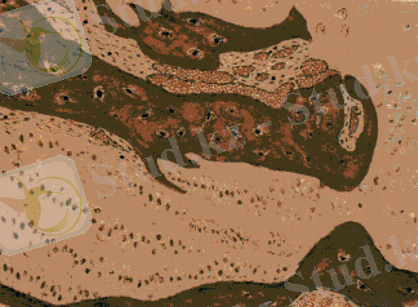

Разросты остеоидной ткани и нерорвная линия

окостенения суставного хряща теленка при рахите.

Патогистологиялық өзгерістер. Рахитке шалдыққан төлдер сүйектерінде туындайтын өзгерістер негізінен остеоидты өрменің шамадан тыс мол пайда болуы, онда кальций тұздарының жеткіліксіз шөгуі және бұрын қалыптасқан сүйектен бұл тұздардың шайылып кетуі түрлерінде болады.